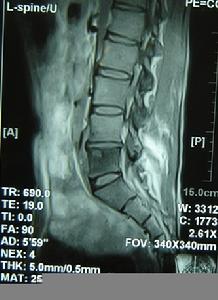

常有病灶雙側根性痛,如枕部痛、頸痛、肩和上肢痛(頸椎);肋間神經痛或束帶樣感覺(胸椎);下肢神經痛(腰椎);並出現相應的脊髓壓迫征和棘突壓痛或叩擊痛、椎旁肌肉痙攣等。全身可有慢性感染症狀,如低熱、消瘦、盜汗、血沉加快等。此外還有下述特點:身體其它部位常有活動性結核病灶;病程一般較短,多在3個月以內。因此,根據病史,臨床表現和X線片(脊柱結核變化)不難作出診斷。必要時作椎管造影、脊髓CT或MRI檢查。

3.脊髓造影顯示散在不規則充盈缺損、杯口狀充盈缺損或神經根袖變形等蛛網膜下腔梗阻表現。MRI對本病的診斷價值很大。